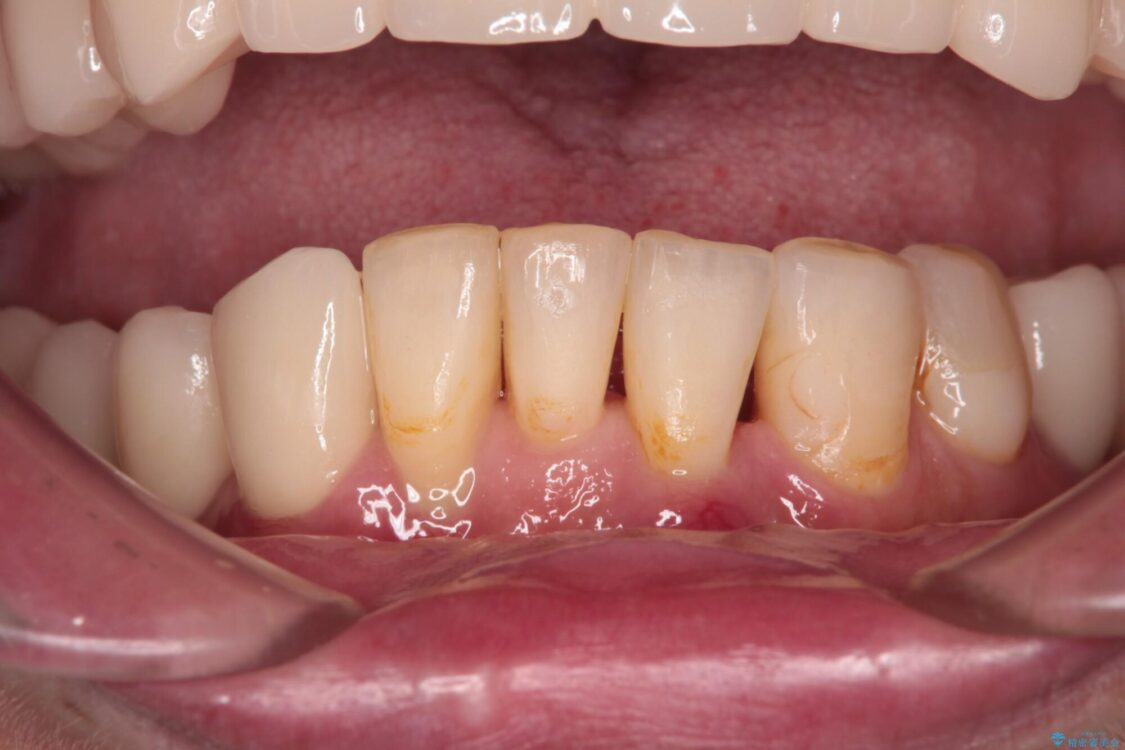

治療前

• 放置したインプラントとインビザライン 全顎リカバリー治療 治療前画像